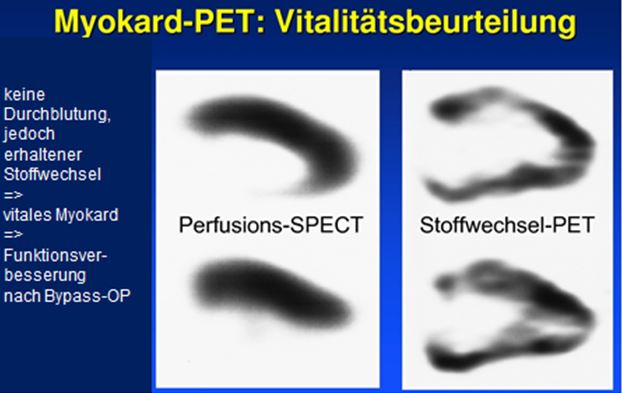

- Kardiologie: Eine PET-CT-Untersuchung erlaubt es, die Myocardvitalität zu beurteilen. Dabei kann festgestellt werden, ob es sich um Narbengewebe, oder um vitales, aber sehr schlecht durchblutetes Myokardgewebe handelt. Denn nur bei vitalen Myocardgewebe bringt eine Bypass-Operation ein Nutzen.